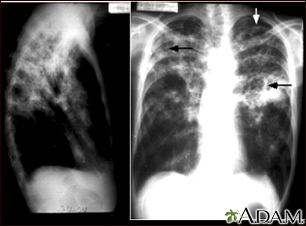

Tuberculosis, advanced - chest x-rays